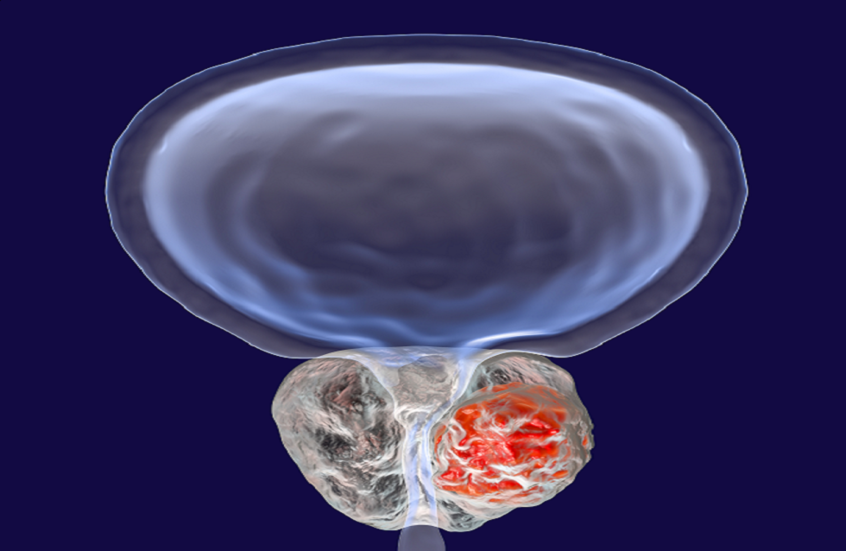

يساهم هذا التفاعل في تسريع تطور سرطان البروستاتا وزيادة نشاطه.

يرتبط ارتفاع نشاط هذا الجزيء بتسارع نمو الأورام، خاصة سرطان البروستاتا.

تشير بيانات دولية إلى أن سرطان البروستاتا من أكثر أنواع السرطان انتشارًا عالميًا.

يتم تشخيص نحو 1.46 مليون حالة سنويًا، مع مئات الآلاف من الوفيات.